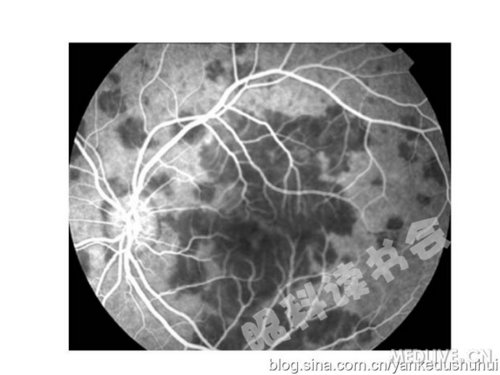

葡萄膜炎最主要的病变部位是脉络膜,脉络膜的主要病理改变是脉络膜毛细血管通透性的增加和充盈状态的改变,造影早期的背景荧光可以反映脉络膜毛细血管的充盈情况;由于RPE是由脉络膜血管供应,脉络膜的病变一般会导致RPE的功能障碍,即血视网膜外屏障的破坏,导致荧光素的渗漏或透见荧光;视盘供血和脉络膜血管均来自于睫状后短动脉,脉络膜的炎症容易影响到视盘,造成视盘血管的屏障破坏,引起荧光素的渗漏;另外部分葡萄膜炎也可以影响视网膜血管,发生炎症细胞的浸润和通透性的增加。

早期的脉络膜背景荧光反应脉络膜毛细血管的充盈情况。早期低荧光是由于脉络膜毛细血管或前小动脉的缺血造成的,晚期由于缺血区域的RPE屏障破坏,造成荧光素的渗漏,表现为边界不清的高荧光。http://webres.medlive.cn/upload/000/062/792

下图为一APMPPE的患者,眼底的主要表现是1/2PD大小左右的鳞状黄白色病灶,可以融合,病变发生于脉络膜毛细血管前小动脉缺血性改变。

http://webres.medlive.cn/upload/000/062/793

早期在脉络膜背景荧光中有与黄白色病灶一致的低荧光。http://webres.medlive.cn/upload/000/062/794

晚期荧光素渗漏出现高荧光。(和VKH一样也是外屏障功能破坏造成荧光素渗漏,但没有发生染料积存的原因是,因为VKH脉络膜的炎症使毛细血管通透性异常增加,渗液更多)